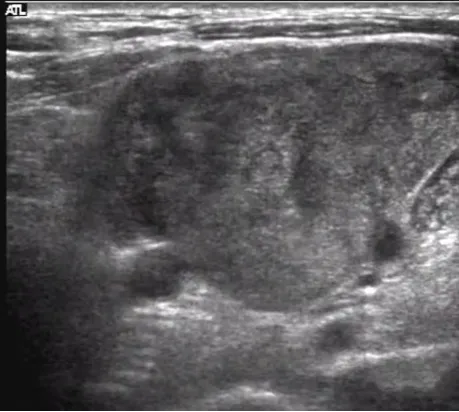

左腋下淋巴结结核样肉芽肿性炎并坏死及钙化。

病例:1岁男孩,发现腋窝包块2个月,质地较硬,患儿无明显发热。

超声描述:左侧腋窝可见两个混合回声团,边界清楚,内部回声不均匀,可见多个强回声点,未见明显淋巴结结构。内部见杂乱血流信号。